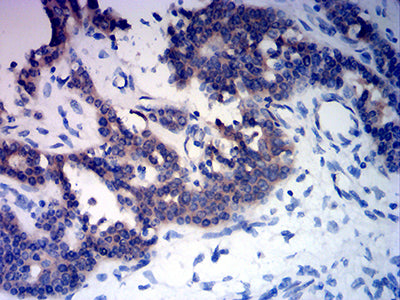

分类: 科研抗体货号: 32201别名: OMR; ORM; ATPM; MOM2; ATP5A; hATP1; ATP5A1; MC5DN4; ATP5AL2; COXPD22; HEL-S-123m应用: WB,IHC,FCM反应种属: Human, Mouse, Rat